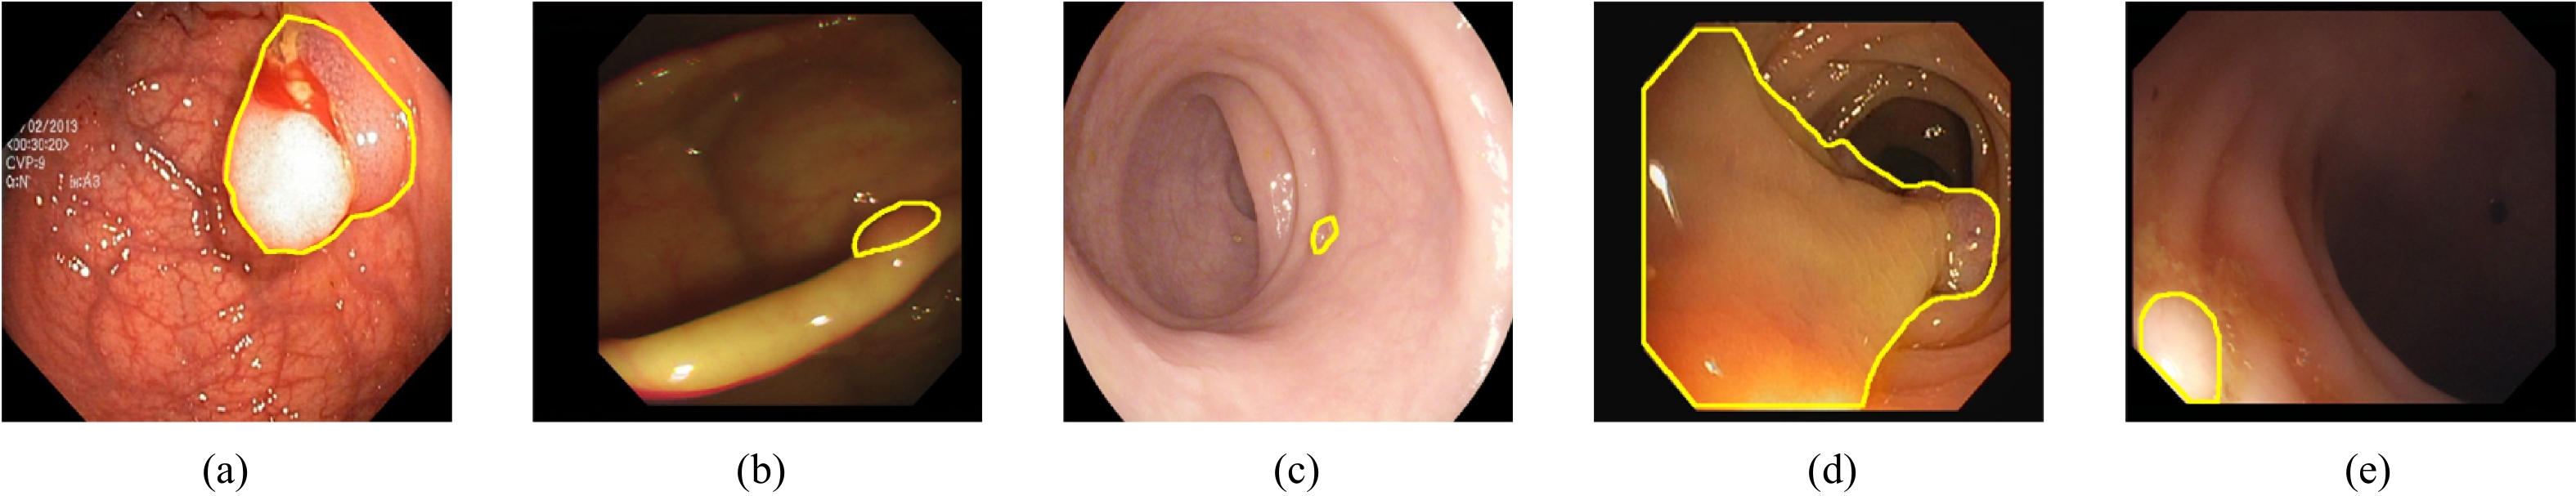

MFAINet: Multi-Receptive Field Feature Fusion With Attention-Integrated for Polyp Segmentation

Guangzu Lv, Bin Wang, Cunlu Xu, Weiping Ding, Jun Liu

2026, 13(4): 822-836. doi: 10.1109/JAS.2025.125408

Abstract(1489) HTML (138) PDF(76)

Abstract:

Colorectal cancer has become a global public health concern. Removing polyps before they become malignant can effectively prevent the onset of colorectal cancer. Currently, multi-receptive field feature extraction and attention mechanisms have achieved significant success in polyp segmentation. However, how to effectively fuse these mechanisms and fully leverage their respective strengths remains an open problem. In this paper, we propose a polyp segmentation network, MFAINet. We design an attention-integrated multi-receptive field feature extraction module (AMFE), which uses layering and multiple weightings to fuse the multi-receptive field feature extraction and attention mechanisms, maximizing the extraction of both global and detailed information from the image. To ensure that the input to AMFE contains richer target feature information, we introduce a multi-layer progressive fusion module (MPF). MPF progressively merges features at each layer, fully integrating contextual information. Finally, we employ the selective fusion module (SFM) to combine the high-level features produced by AMFE, resulting in an accurate polyp segmentation map. To evaluate the learning and generalization capabilities of MFAINet, we conduct experiments on five widely-used public polyp datasets using four evaluation metrics. Notably, our model achieves the best results in nearly all cases.